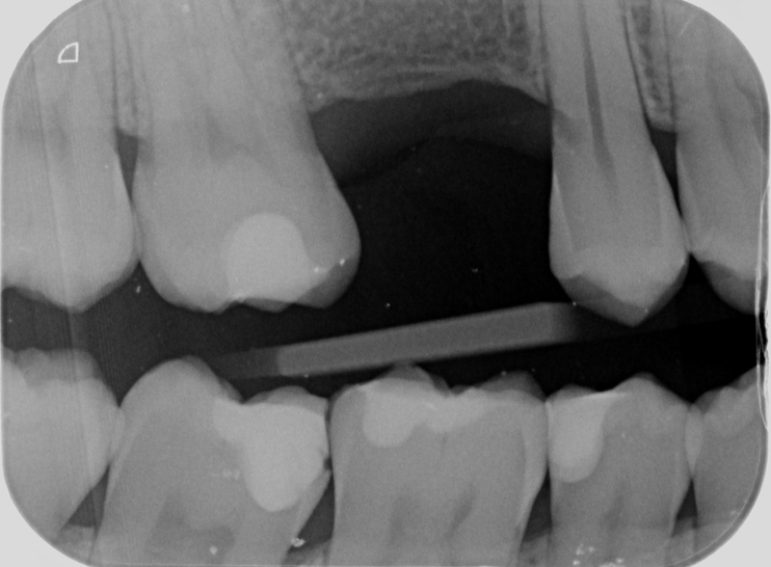

External Cervical Resorption on UR5